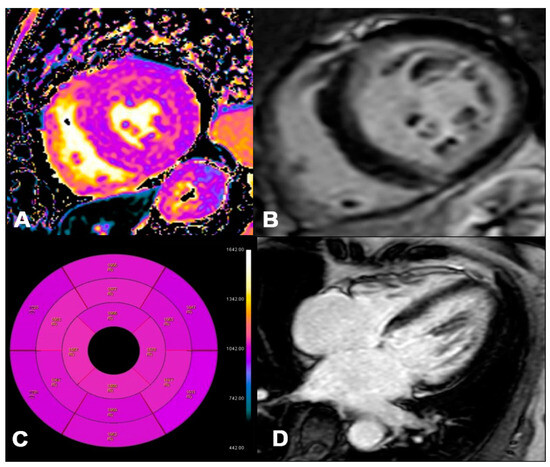

Figure 7.

ATTR 73-year-old patient diagnosed with endomyocardial biopsy. T1 Native Mapping (A) demonstrates abnormally high values in all entire LV walls in cardiac amyloidosis. Diffuse transmural LV and subendocardial RV LGE in two-chamber short (B) and long axes (C). Bullseye map of T1 Native (D).